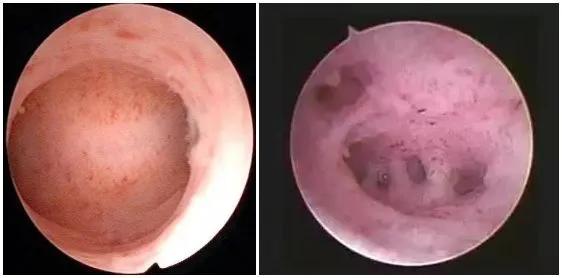

宫腔黏连

子宫内膜息肉